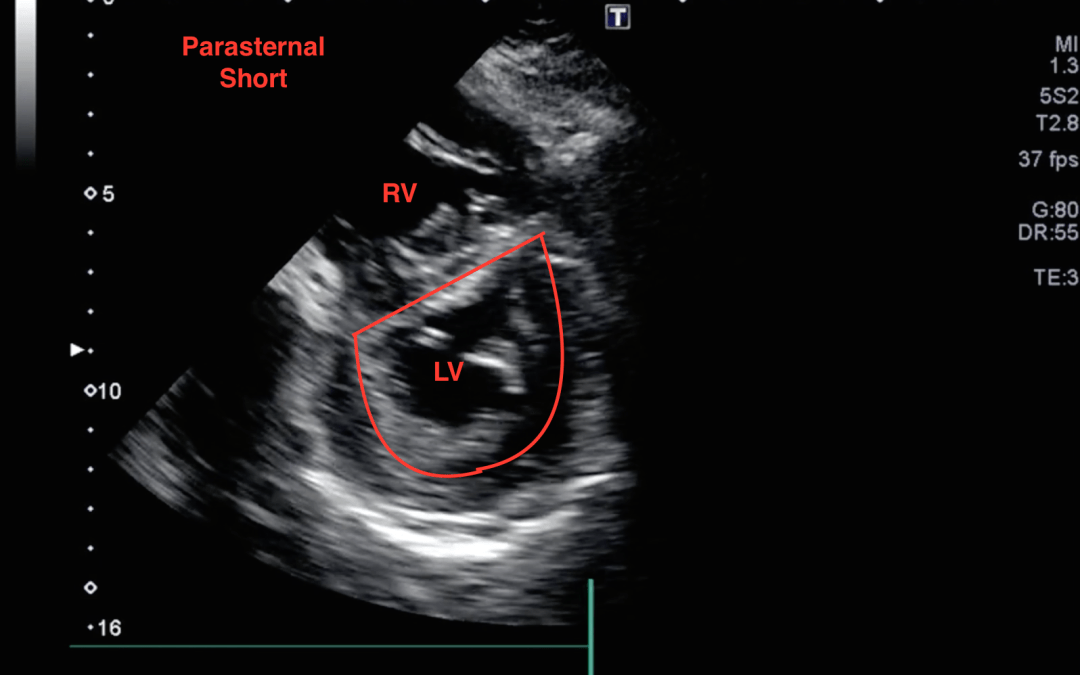

Here is a parasternal short view:

This is an impressive view because a d-sign is appreciated. A d-sign is an indication that the right-sided ventricular pressures are higher than the left ventricular pressures causing septal bowing. Wonder why it is called a d-sign? See below: